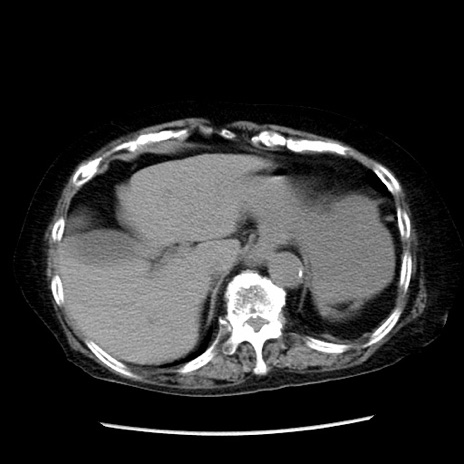

症例14(横断像)

【症例】 90歳代女性

【主訴】 腹痛・嘔吐

【現病歴】今朝から左側腹部痛を認めた。 経過観察していたが、嘔吐を認めたため来院。

【既往歴】 子宮癌術後

【身体所見】 意識清明、BP 127/54mmHg、P 98bpm Sp02 95%(RA)、BT 35.8°C、腹部平坦・軟腸ぜん動音聴取良好、右下腹部圧痛(+) 反跳痛なし

【データ】WBC 9800、CRP 0.46